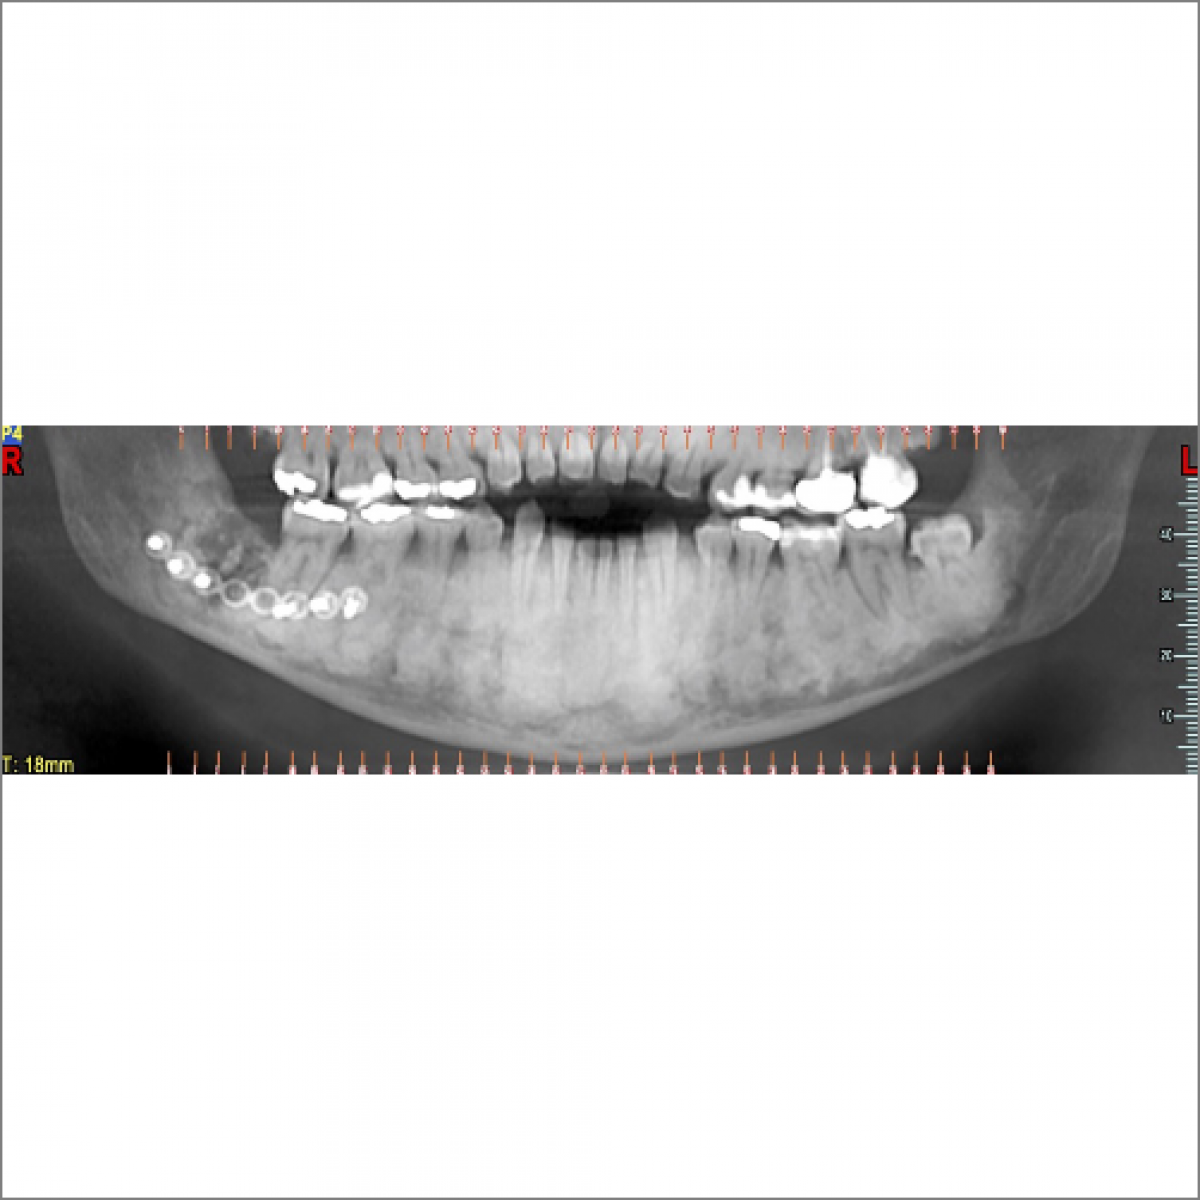

The aim of this paper is to perform a literature review regarding the Gnathodiaphyseal Dysplasia (GDD), describing two clinical cases.

Gnathodiaphyseal Dysplasia is a rare autosomal dominant syndrome caused by mutation in the ANO 5 gene. The most frequent clinical signs are: maxillary fibro-osseous lesions, bone fragility, diaphyseal cortical thickening and bowing of long bones. However, there is great variability between patients. Genetic screening is at present the only reliable diagnostic tool. Gnathodiaphyseal Dysplasia is a rare genetic syndrome that requires in-depth study and a multidisciplinary team.